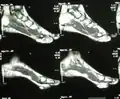

| Angiolipoma foot | |